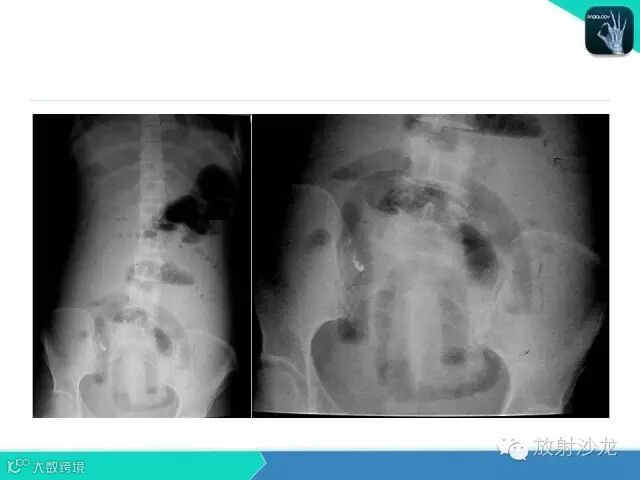

肠梗阻的分类及影像诊断